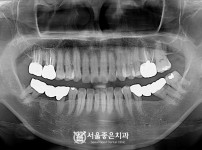

303

뼈이식 임플란트 2개 - 오스템 임플란트 / 기존 브릿지 2차우식

구분 임플란트